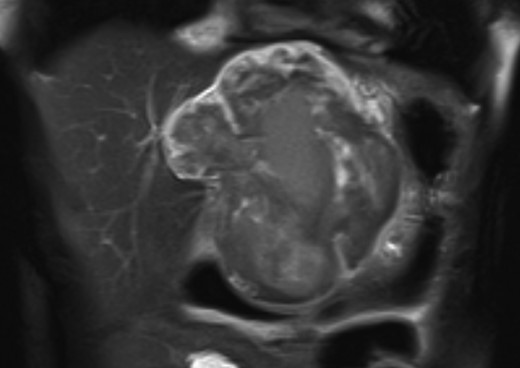

An 18-year-old woman presented with epigastric pain that started during a Japanese drum lesson. She was diagnosed with rupture of a hepatic tumor and transported to our hospital. She had no medical history of surgery, including abdominal surgery. Contrast-enhanced computed tomography (CT) revealed a 13-cm, low-density giant mass in the left hepatic lobe and high-density ascites, indicating abdominal bleeding from the liver tumor (Fig. 1). Ultrasonography confirmed a well-defined giant mass of the liver, comprising both cystic and solid lesions. Laboratory data showed a low hemoglobin level of 8.2 g/dl, and all the results of liver function tests and tumor marker measurement were within normal ranges. The patient underwent emergent celiac angiography, which revealed an avascular tumor with no evidence of extravasation from the hepatic artery. The left hepatic artery was considered to be the artery feeding the tumor and was embolized (Fig. 2). Magnetic resonance imaging (MRI) confirmed a well-defined giant multilocular lesion with fibrous partition (Fig. 3). After the patient's condition stabilized, she underwent left hepatic lobectomy. Laparotomy revealed bloody ascites and a large tumor in the left lobe of the liver; the right lobe appeared normal. The enlarged lymph nodes of the hepatoduodenal ligament were also dissected. Histological analysis of the resected specimen revealed a huge cystic mass of ∼12 × 9.5 cm. The mass was cystic and multilocular with a fibrous wall and filled with a massive blood clot (Fig. 4). The enlarged lymph node had a 25 × 23-mm cyst, which contained yellowish fluid. On microscopic examination, the wall of the cyst consisted of a tight elastic fiber meshwork composed of collagen fibers, which was accompanied by a small amount of acid mucopolysaccharide in the stroma and a lining of single-layered flat cells on the inner wall (Fig. 5a and b). Immunohistochemical staining revealed that the cyst wall was positive for both the endothelial marker CD31 and the lymphangial marker D2-40 (Fig. 5c and d). The cystic structure of the lymph node also was composed of elastic fiber components similar to those of the cyst in the liver and lined with single-layered flat cells, which were immunohistochemically positive both for CD31 and D2-40 (Fig. 5e). The pathological diagnosis was hepatic lymphangioma combined with lymphangioma of the lymph nodes. The patient's postoperative course was uneventful, and she was discharged on Day 8. During follow-up for almost 4 years since the surgical treatment, the patient has presented no sign of recurrence.

MRI confirmed a well-defined giant multilocular lesion with fibrous partitioning.